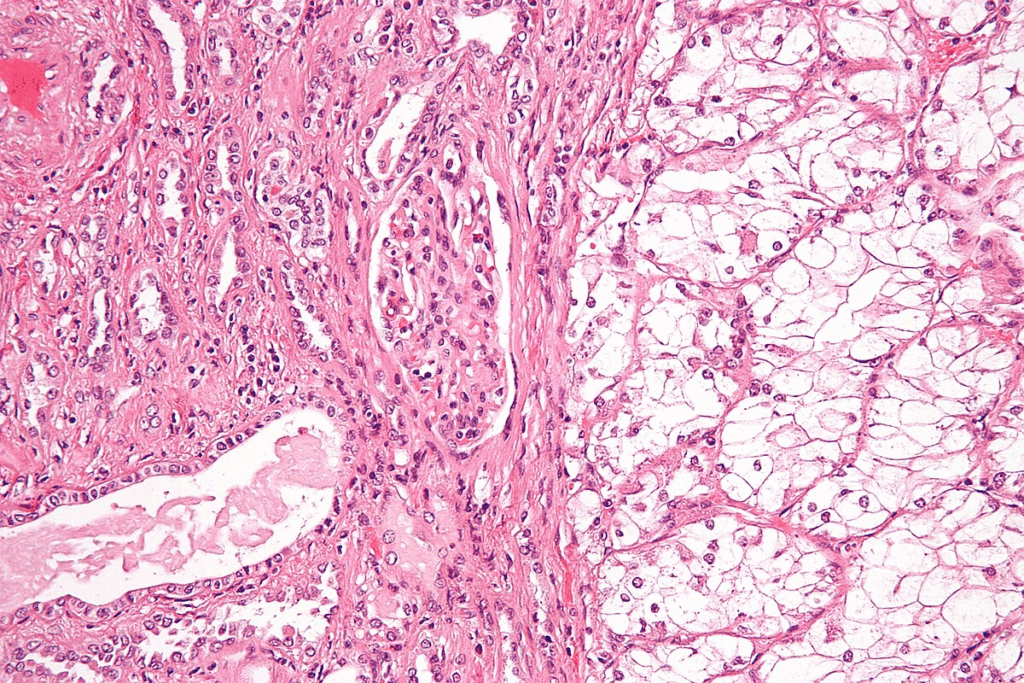

Cryoablation, or cryotherapy, uses extreme cold to kill cancer cells. For kidney tumors, a probe is inserted under imaging. It emits very low temperatures, killing the tumor cells.

How Cryoablation Works for Kidney Tumors

The process starts with local anesthesia or sedation to reduce pain. Then, under imaging, a cryoprobe is placed in the tumor. The probe is turned on, freezing the tumor.

Freezing and thawing are done twice to make sure the tumor is fully destroyed. This method kills tumor cells without harming the healthy kidney tissue.